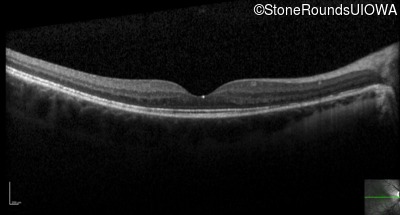

Optical Coherence Tomography - Right - 20/40 +1

Exemplar / OCT Stack